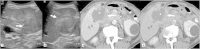

Malignancies of the biliary tract include cholangiocarcinoma, gallbladder cancers and carcinoma of the ampulla of Vater. Biliary tract adenocarcinomas are the second most common primary hepatobiliary cancer. Due to their slow growing nature, non-specific and late symptomatology, these malignancies are often diagnosed in advanced stages with poor prognosis. Apart from incidental discovery of gall bladder carcinoma upon cholecystectomy, early stage biliary tract cancers are now detected with computed tomography (CT) and magnetic resonance imaging (MRI) with magnetic resonance cholangiopancreatography (MRCP). Accurate characterization and staging of these indolent cancers will determine outcome as majority of the patients' are inoperable at the time of presentation. Ultrasound is useful for initial evaluation of the biliary tract and gallbladder masses and in determining the next suitable modality for further evaluation. Multimodality imaging plays an integral role in the management of the biliary tract malignancies. The imaging techniques most useful are MRI with MRCP, endoscopic retrograde cholangiopancreatography (ERCP), endoscopic ultrasound (EUS) and positron emission tomography (PET). In this review we will discuss epidemiology and the role of imaging in detection, characterization and management of the biliary tract malignancies under the three broad categories of cholangiocarcinomas (intra- and extrahepatic), gallbladder cancers and ampullary carcinomas.